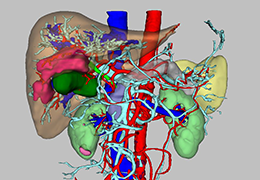

ANYTHINK 经导管主动脉瓣膜置换术分析系统